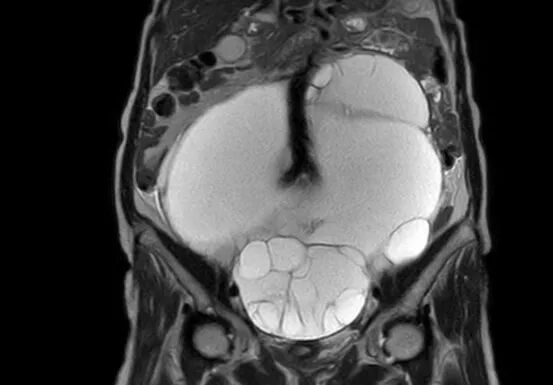

72岁的邓阿婆,平时身体硬朗,每年定期体检,却独独没有做妇科体检。一段时间以来,邓阿婆察觉到自己的肚子越来越大,起初以为是自己长胖了就没在意。直到家人发现邓阿婆的肚子大得如同怀孕七八个月,才于近日带她到珠海市第五人民医院就诊。经过彩超检查及MRI检查,发现一个巨大肿瘤完全占据了邓阿婆的盆腹腔,大小约252mm*223mm*94mm,犹如一个大西瓜。同时,医生还发现邓阿婆患有宫颈高级别鳞状上皮内瘤变(CINIII,宫颈癌前病变)。

针对邓阿婆的病情,市五院妇产科组织全院多科室会诊。经过全面的评估与讨论,制定了缜密的手术方案。在充分做好术前准备后,市五院妇产科副主任刘小红带领团队迅速为邓阿婆实施巨大肿瘤切除及全子宫切除术。术中,妇产科团队克服患者盆腔肿物巨大暴露困难、与周围组织黏连紧密等不利因素,在麻醉医师与手术室高效协同配合下,手术过程顺利,完整切除7斤重的盆腔肿瘤。冰冻病理结果提示卵巢浆液性囊腺瘤,为良性肿瘤,等在手术室外的家属得知结果后,悬着的心终于放了下来。此次手术,手术团队同时解决了邓阿婆巨大肿瘤问题和宫颈癌前病变问题。术后,在医护团队的专业精心护理下,邓阿婆不仅感觉腹部轻松了,心情也放松了,身体很快恢复如常,日前已顺利康复出院。“我现在吃饭、睡觉、走路,感觉一身轻松,重获新生的感觉真好!”困扰自己的大肚子消失了,邓阿婆露出了开心的笑容。为表示感谢,邓阿婆和家属专程送来一面鲜红的锦旗,并向刘小红副主任及妇产科团队紧紧握手致谢。